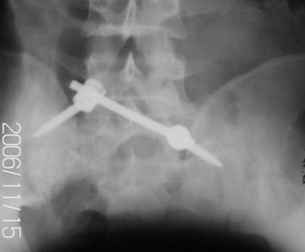

Уважаемые коллеги! 27 июля 2006г. представлял на форум больного со сложным застарелым переломом таза. Сейчас провели контрольное обследование.

Результат представляю в картинках.

Фиксация сзади выполнена системой "Силует" фирмы "Зиммер", предназначенной для транспедикулярной стабилизации позвоночника. Юрий Алексеевич Булахтин